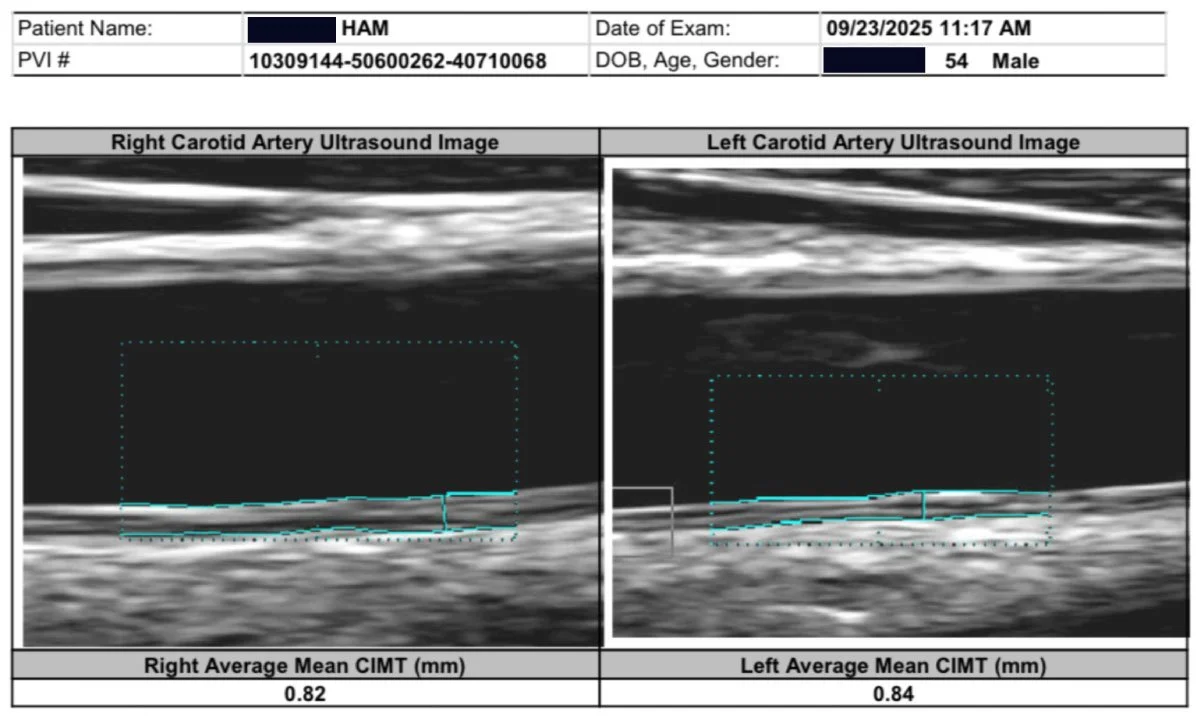

And here is what reversal looks like. My carotid plaque. Gone. Remodeled. In three months. Bilateral carotid IMT of 1.8 mm and 1.6 mm with visible plaque on both sides, dropping to 0.84 mm and 0.86 mm with no visible plaque detectable on ultrasound. My CT-FFR on a dominant D1 diagonal with 77 percent stenosis: improved from 0.75 to 0.80, crossing from ischemic into the normal range. LDL: 61, a 64 percent reduction. ApoB: 45. The word my physician friends used: Unbelievable!

After: Plaque remodeling and reversal. B-mode ultrasound imaging of the carotid artery. Kevin Ham, MD, 2025. Three months on the CAST protocol: WFPB diet, high-intensity cycling, structured fasting, targeted supplementation.